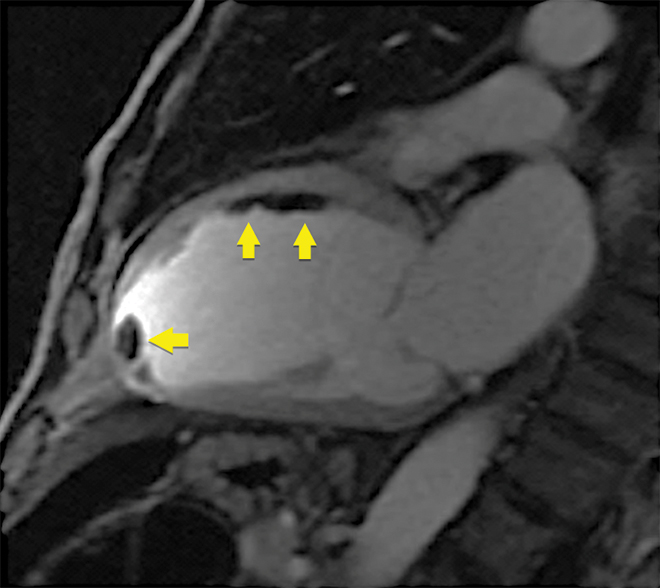

Clinical vignette 3: A 74-year-old man with a late-presentation ST-elevation myocardial infarction is shown to have an occluded left anterior descending artery during coronary angiography. Echocardiography shows an ejection fraction of 40%. Cardiovascular magnetic resonance (CMR) demonstrates that the anterior wall is akinetic, with full thickness infarction and no residual viable myocardium. Based on this information, he does not undergo stenting or coronary artery bypass graft surgery and is treated medically with heart failure therapy.

CMR imaging: two-chamber view showing a dilated left ventricle with akinetic anterior wall (A), and post-contrast imaging showing full thickness infarction of the entire anterior wall with no residual viable myocardium (B, arrows).